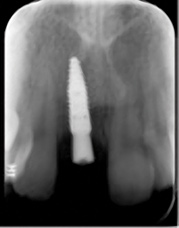

The patient returned at 4 months postoperatively for site evaluation (Figure 11). Bone sounding with an anesthetic needle indicated formation of hard bony surface. At 4 months lamellar bone is present.7 A cone-beam computed tomography (CBCT) scan of site No. 8 radiographically confirmed that the bony ridge had been regenerated (Figure 12). CBCT measurements indicated the maxillary ridge was 6.44 mm wide and 21 mm tall.

Fig 12. CBCT at 4 months postoperative showed vertical bone regeneration.

Figure 12

Fig 16. Implant radiograph on day of insertion.

Figure 16